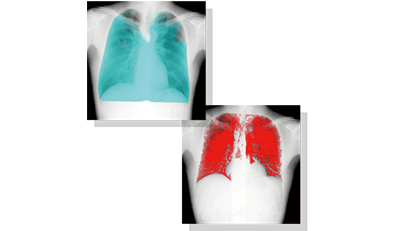

技術紹介 胸部動態解析技術

従来の単純X線撮影と同様の設備で、肺機能の可視化、定量化を可能とする新たな胸部診断手法の実現を目指して、コニカミノルタは今、単純X線撮影による胸部動態解析技術の開発に取り組んでいます。

従来の静止画による解剖学的な画像所見による診断から、動画像による機能診断の実現に向けたコニカミノルタの挑戦をご体感ください。

- 単純X線撮影で実現する胸部動態解析技術